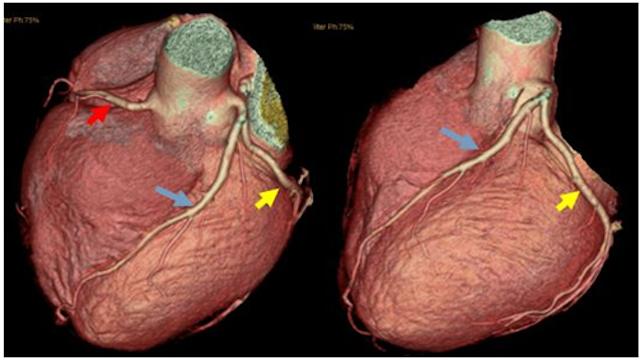

La naissance de la tomodensitométrie à 64 rangs et le développement de la technologie de suivi dynamique nous ont permis d'examiner les vaisseaux cardiaques de manière non invasive afin d'identifier la présence et l'étendue de la sténose dans les vaisseaux coronaires. Cette technique a bénéficié à de nombreux patients souffrant d'oppression et de douleurs thoraciques et ayant peur des aiguilles et du bloc opératoire. Le principe de cet examen est le suivant : un agent de contraste est injecté par voie intraveineuse et un balayage en spirale des vaisseaux coronaires remplis de produit de contraste est effectué par tomodensitométrie. Chaque tranche de balayage de l'artère coronaire est ensuite combinée pour former une image de l'artère coronaire grâce à la technologie de combinaison d'images.

Ce test est non invasif et sûr, mais il présente un certain nombre de lacunes, ① le contrôle du rythme 64 rangs CT exige que la fréquence cardiaque soit contrôlée à 60 battements / min ou moins, plus rapide 128 rangs et CT à double source exige également que la fréquence cardiaque soit contrôlée autant que possible dans les 70 battements / min ou moins ; ② Coronary CT entre le cœur de l'examen ordinaire et l'angiographie des artères coronaires, mais aussi et l'angiographie des artères coronaires, comme les dommages de rayonnement et de contraste, si les symptômes sont très clairs. Si les symptômes sont très clairs, il est préférable d'effectuer le test d'imagerie en plus de l'examen, qui peut également être traité directement ; ③ souvenez-vous de cette phrase, si le scanner coronaire indique que vous n'avez pas de maladie coronarienne, la crédibilité de cette phrase peut atteindre 99 %, mais si le scanner coronaire indique que vous avez une maladie coronarienne, la crédibilité de cette phrase n'est que de 70 %.

5. angiographie coronaire par tomodensitométrie (CT coronary angiography)La procédure consiste à injecter un agent de contraste iodé dans un vaisseau sanguin. Elle consiste à injecter un agent de contraste iodé dans un vaisseau sanguin et à utiliser la tomodensitométrie (CT) pour examiner les artères coronaires afin de vérifier la présence de malformations, de ponts dans le myocarde, de plaques et de sténoses dans les artères coronaires. L'avantage de cette méthode est qu'elle est "non invasive" et qu'il n'est pas nécessaire d'introduire un cathéter dans les artères coronaires. Cependant, comme il s'agit d'une radiographie, il est préférable d'examiner les calcifications, mais il y a des limites à l'examen des sténoses, qui n'est pas très précis (cela dépend de l'instrument et du niveau de compétence de l'examinateur), et en outre, un rythme cardiaque rapide ou irrégulier affectera également l'effet de l'imagerie. Par conséquent, cette méthode est la meilleure pour exclure une maladie coronarienne et moins précise pour diagnostiquer une sténose. En outre, au cours de l'examen, 80 à 100 ml d'agent de contraste iodé sont injectés par voie intraveineuse. Premièrement, il existe un risque d'allergie (le test cutané peut ne pas être détecté), deuxièmement, l'agent de contraste doit être excrété par les reins, ce qui est dommageable pour les reins, et un petit nombre de patients peut développer une "néphropathie de contraste" (néphropathie de contraste), avec une déficience ou une insuffisance rénale, de sorte qu'un traitement d'"hydratation" est nécessaire avant et après l'examen. Il est donc nécessaire de s'hydrater avant et après l'examen.

- 冠Le CTA de Pulse est un plombier débutantL'angiographie coronarienne est en fait une sorte d'examen tomodensitométrique. Lors de cet examen, un médicament est injecté dans la veine de la main, ce médicament est l'agent de contraste. Lorsque l'agent de contraste atteint l'artère coronaire, il montre l'ombre de cette artère coronaire et permet de déterminer s'il y a un blocage ou un rétrécissement de l'artère coronaire.Les troncs principaux des artères coronaires et certaines des plus grosses branches sont plus clairement visibles, tandis que les plus petites branches sont moins bien représentées.

ATC coronaire

L'angiographie coronarienne par tomodensitométrie est un moyen d'examiner les artères coronaires en combinaison avec l'angiographie, ce qui permet de diagnostiquer la maladie coronarienne et d'examiner et de juger l'emplacement des plaques coronaires, en particulier l'étendue des plaques calcifiées. L'angiographie coronarienne par tomodensitométrie permet également d'évaluer si le flux sanguin est régulier au niveau du site du stent chez les patients atteints de maladie coronarienne et auxquels on a implanté des stents. En outre, pour les patients souffrant de douleurs thoraciques, l'angiographie coronarienne par tomodensitométrie permet de détecter des problèmes tels que l'aortique, le pneumothorax et le pneumothorax. Pour les patients souffrant de douleurs thoraciques, l'angiographie coronaire peut être utilisée pour dépister les problèmes aortiques, pulmonaires et de pneumothorax, mais elle n'est pas recommandée pour les patients présentant une forte suspicion d'infarctus aigu.

Cependant, pour une partie de la population qui ne présente pas de risque élevé de maladie coronarienne, les médecins recommandent parfois un dépistage de la sténose des artères coronaires à l'aide de la technologie CTA coronaire.Bien que la précision de l'angiographie coronaire soit encore loin de celle de la coronarographie, elle permet d'exclure les patients dont la coronaropathie est négative.